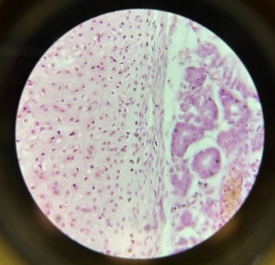

Trachea

Trachea

Trachea

Trachea

Trachea

Trachea

Trachea

Trachea

Trachea